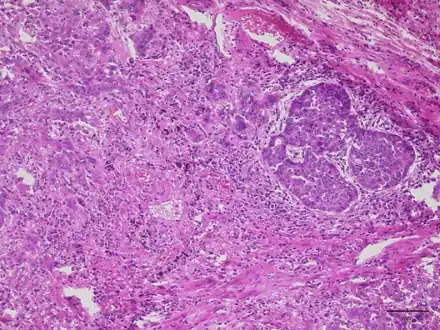

Lung adenocarcinoma with Lambert Eaton myasthenic syndrome-lesion shows proliferation of infiltrating atypical epithelial cells with cribriform or papillary structures

Lung adenocarcinoma with Lambert Eaton myasthenic syndrome-lesion shows proliferation of infiltrating atypical epithelial cells with cribriform or papillary structures Chest X-ray showing a tumor in the left lung (right side of the image)